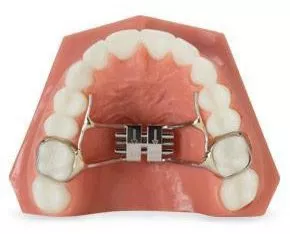

מכשיר לתזוזת שיניים לכיוון אחורי – פנדולום

מכשור הנקרא Pendulum מטרתו לבצע תנועת דיסטליזציה (לכוון אחורי) של הטוחנות העליונות ובכך לפנות מקום באזור הקדמי. מכשור זה מודבק בחלק הפנימי של הלסת, באזור החך, ומשך הזמן המוערך לשלב זה הוא כ-3 עד 6 חודשים.